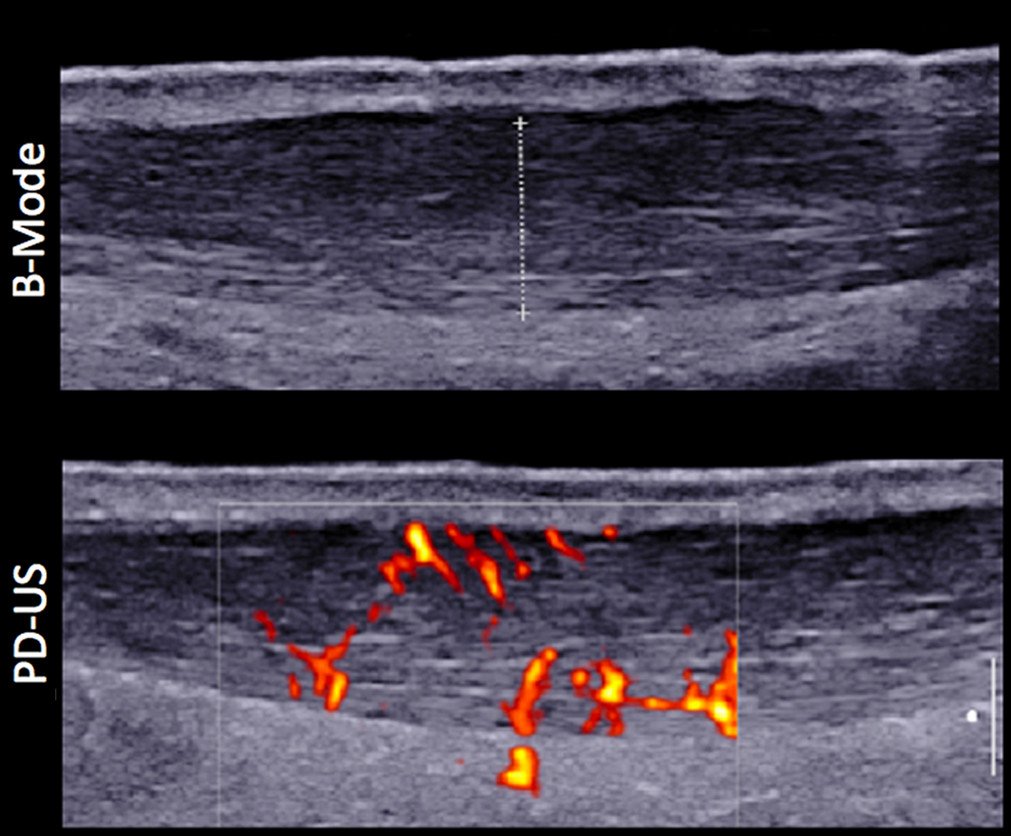

Ultrasound image of mid-portion Achilles tendinopathy (thickened tendon with abnormal fiber architecture with neovascularization). Courtesy of Gatz et al., Orthopaedic Journal of Sports Medicine, 2021